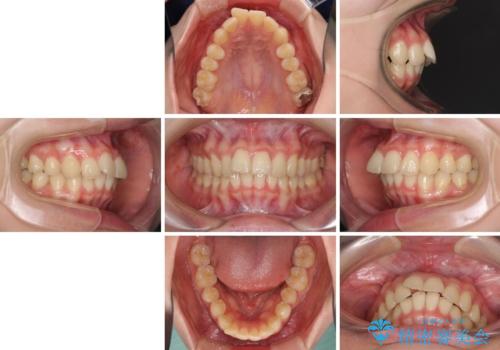

飛び出した前歯と黄ばんだ歯 ホワイトニングしながらマウスピース矯正

- 前歯2本が飛び出してることを気にして来院された患者様です。

全体的に黄ばんだ歯の色も気になるとのことで、マウスピース矯正により飛び出した前歯を治しつつ、ホームホワイトニングを併用して黄ばみを解消していくこととしました。

歯と歯の間を削ることで、飛び出した前歯が引っ込み、スッキリとした口元となりました。

歯の黄ばみも改善され、明るい歯並びとなりました。